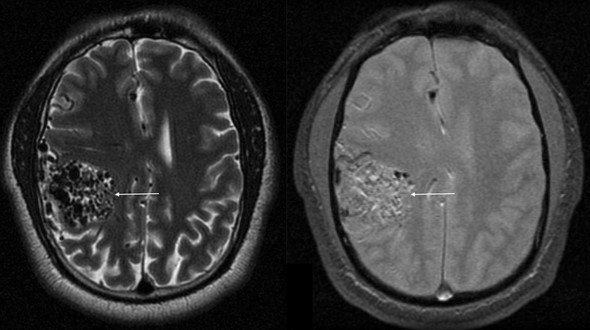

Иллюстрации и пояснения: гиподенсивный очаг на КТ головного мозга